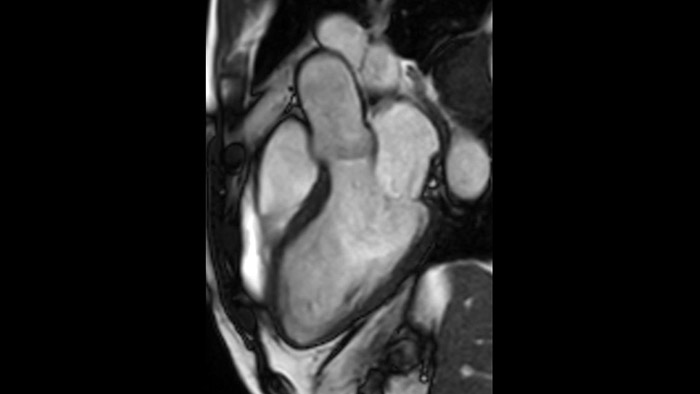

Quantify Myocardial Strain

IntelliSpace Portal MR Caas5,6 Strain7 assists in patient diagnosis and monitoring by providing global strain parameters such as global longitudinal strain (GLS), global circumferential strain (GCS), and global radial strain (GRS), using short and long axis MR images, as well as describing the myocardium deformation- such as shortening, thickening, and lengthening during the cardiac cycle.